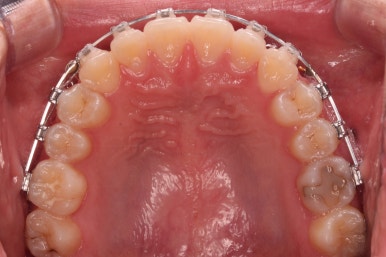

각설하고 위의 사진들은 부산치아교정잘하는곳 키다리아저씨치과에서 처음 내원하셨을 때의 사진입니다.

입매는 크게 나쁘진 않았으나 아랫입술-턱끝까지 이어지는 S라인이 너무 깊어 아랫입술이 약간 뒤집어진 형태를 보였어요.

그리고 오른쪽 위 송곳니가 덧니처럼 볼록하여 웃거나 말할 때 자신감 있게 입을 벌리지 못하고 있었어요.

아랫니는 크게 심하지 않았고 윗니 앞니쪽에 치열이 삐뚤한 것을 볼 수 있어요.

그리고 위아랫니의 중앙선도 어긋나 있는 것으로 봐서 왼쪽과 오른쪽의 교합 자체도 다르고 문제가 있음을 알 수 있었어요.

각각 왼쪽, 오른쪽의 교합의 모습입니다.

가장 좋은 교합은 위아래 치아들이 지그재그로 톱니바퀴 물리듯이 맞아들어가야 하는데 오른쪽 사진들 보면 중간중간 빈틈도 많이 보여요.

이런 교합은 장기적으로 치아 수명을 단축시킬 수 있습니다.